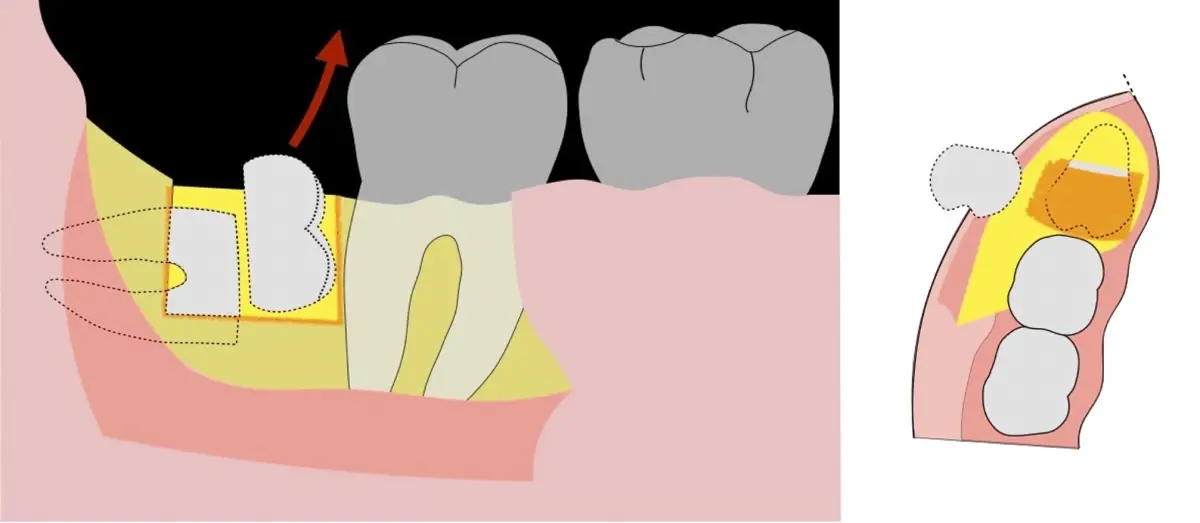

Figura 5. Fractura y eliminación oclusal del fragmento óseo de la porción coronal oclusal.

Figura 6. Demarcación y fractura de la zona de osteotomía a nivel vestibular con inserto aserrado recto y/o angulado.